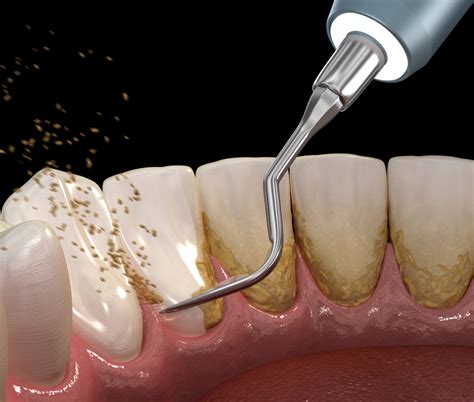

En Clínica Dental Letamendia, empleamos tecnología de ultrasonidos de última generación para quitar el sarro de los dientes de manera precisa y confortable. El proceso incluye también el uso de instrumental manual especializado (curetas) para el refinado de superficies radiculares y la eliminación de sarro en áreas de difícil acceso.

El tratamiento básico para eliminar el sarro se denomina tartrectomía, profilaxis o limpieza dental profesional y lo debe realizar un dentista experto. La limpieza consiste en un raspado coronal indoloro, por lo que se realiza sin anestesia. El dentista en Salamanca o higienista dental lo hace de forma manual.

Asimismo, el sarro puede extraerse con un aparato que emite ultrasonidos que lo desintegran.

En el caso de que el sarro se haya acumulado bajo las encías, es necesario realizar un curetaje o raspado dental. Este implica una limpieza más profunda, que sí suele requerir la aplicación de anestesia local.